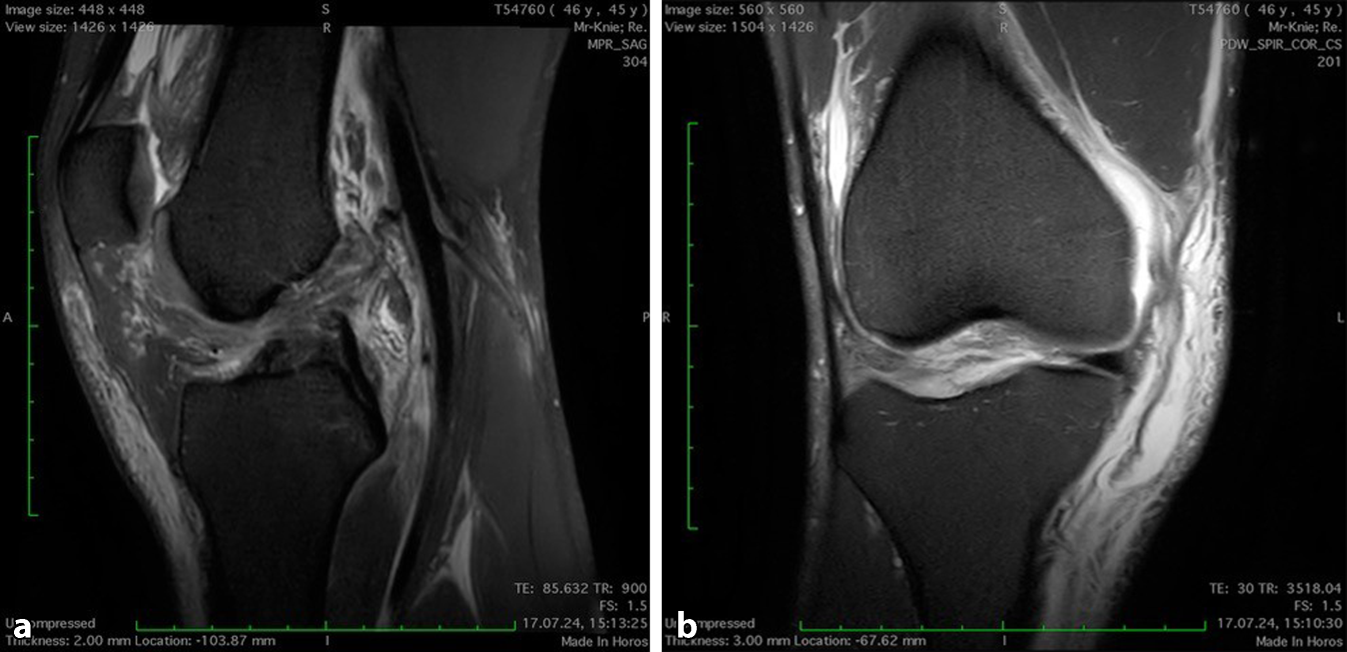

Wir berichten über einen 45-jährigen Patienten mit einer komplexen Verletzung des rechten Kniegelenks nach einem Sturz beim Skateboarden. Es wurde ein Riss des vorderen Kreuzbands sowie des Innenbands (III°) mitsamt Avulsion der anteromedialen Gelenkkapsel von der Tibia diagnostiziert, woraus eine deutliche anteromediale Rotationsinstabilität des Kniegelenks resultierte (MRT siehe Abb. 1).

Abb. 1

MRT der Verletzung. a Komplexe Innenbandruptur mit tibialem Ausriss des MCL mitsamt anteromedialer Kapsel. b LCA-Ruptur